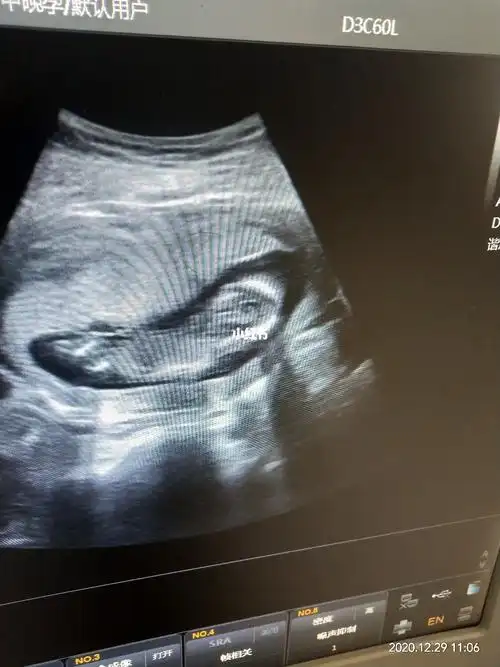

图片还没什么感觉,b超室里看到动态的样子,老母亲真的很激动!

怀孕16周胎儿发育什么样子,如果引产,胎儿还能存活下来吗?

宝宝孕16周了,一切检查秒过,健康男孩宝一枚,儿女双全太幸福了

孕16周胎儿发育情况-孕16周胎宝宝发育指标

孕16周时b超发现胎儿腹裂,羊穿结果显示正常,医生却说不容乐观